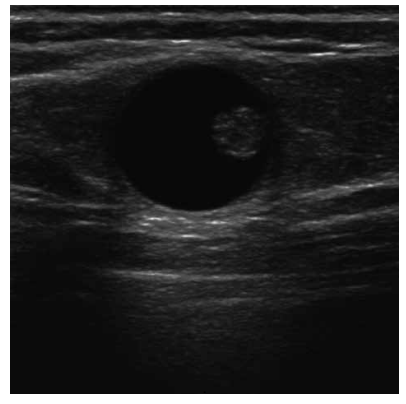

Uma paciente de 52 anos realiza ultrassonografia de mamas de rotina. O exame evidencia uma alteração focal na mama esquerda, conforme mostrado na figura a seguir:

Com base nesse achado, assinale a alternativa que melhor descreve o padrão ultrassonográfico observado e sua classificação BI-RADS.